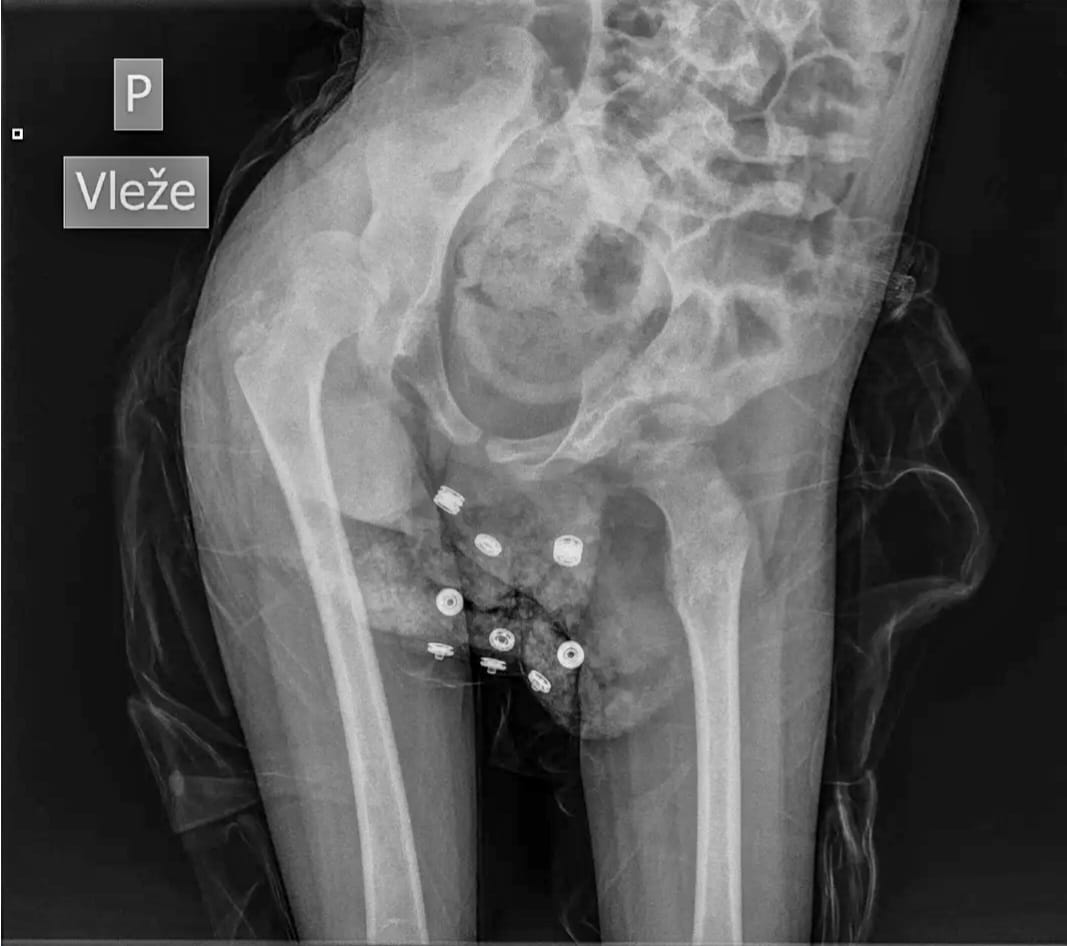

18.10. jsem měl 8.narozeniny, děkujeme Všem za milá přání. Jeden dárek jsem dostal i v Motole, po 4letech mi vyměnili peg v bříšku. V plné narkóze, tak jsme měli trochu strach co bude po probuzení, ale vše dobré. Dostal jsem nové léky na překyselení žaludku(někdy je mi trochu cítit z pusy a zlobí mě reflux) a….nějak mi lépe sedl a ležím i na bříšku.